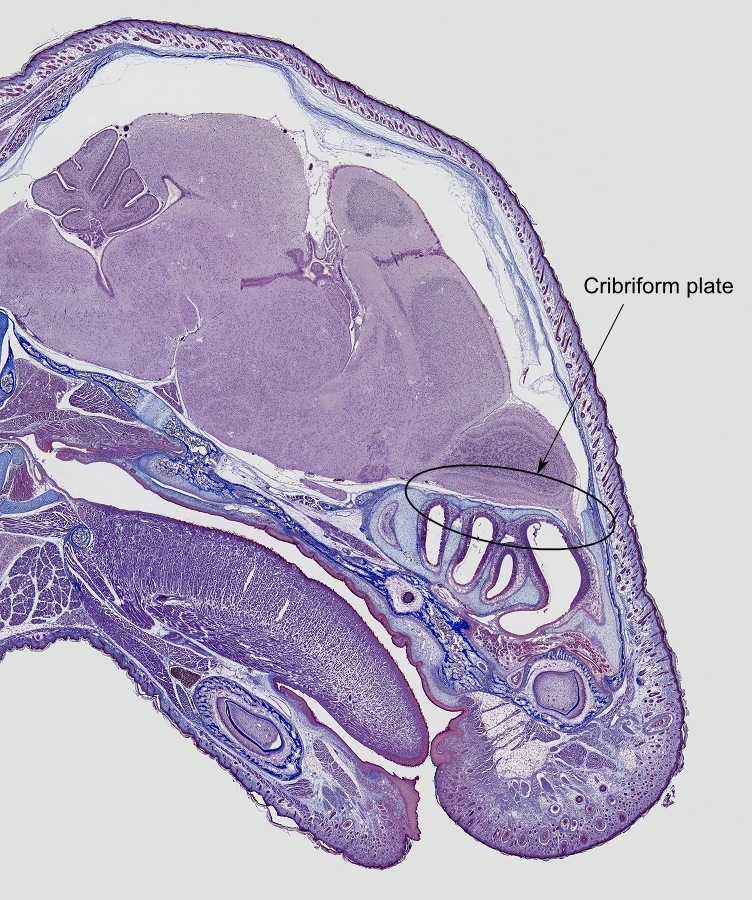

Hier ein Bild die ich gestern mit ein 4x Objektiv und das LED genommen habe. Ist doch Prima homogen ausgeleuchtet. Sind 46 Bilder die gestitched sind.

nun, die LED-Lösung von Stephan Hiller sind schon "erste Sahne"! Genau wie Dein Bild vom Mauskopf. Das ist von einer fast unglaublichen Qualität. Gibt es das Bild auch als "Zoomify"?